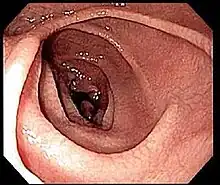

Endoscopy

An upper endoscopy with biopsy of the duodenum (beyond the duodenal bulb) or jejunum is performed to obtain multiple samples (four to eight) from the duodenum. Not all areas may be equally affected; if biopsies are taken from healthy bowel tissue, the result would be a false negative.[40] Even in the same bioptic fragment, different degrees of damage may be present.[16]

Most people with coeliac disease have a small intestine that appears to be normal on endoscopy before the biopsies are examined. However, five findings have been associated with high specificity for coeliac disease: scalloping of the small bowel folds (pictured), paucity in the folds, a mosaic pattern to the mucosa (described as a "cracked-mud" appearance), prominence of the submucosa blood vessels, and a nodular pattern to the mucosa.[96]